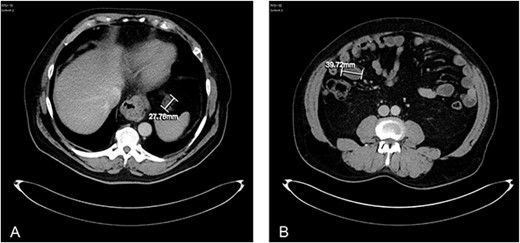

Axial CT abdomen with contrast demonstrating an appendiceal mass of maximum diameter 51.96 mm.

Axial CT abdomen with contrast demonstrating a peritoneal deposit posterior to the descending colon in the left iliac fossa, measuring 37.15 mm.